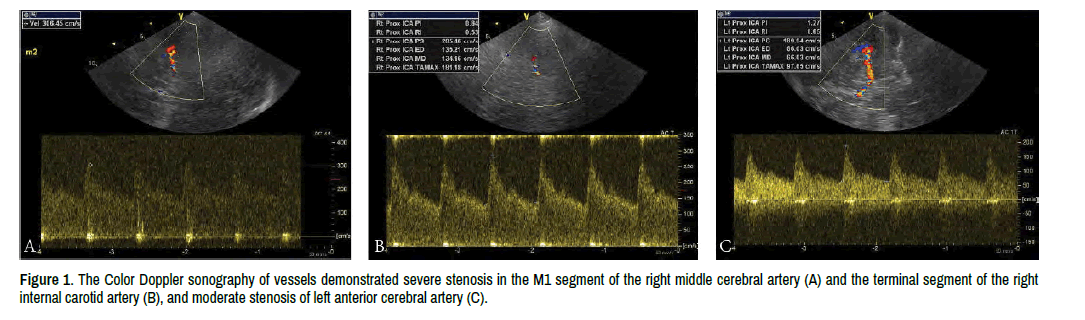

In May, 2020, about 1 week after the sixth cycle of chemotherapy, the patient developed symptoms of fever, headache and a short convulsion with unconsciousness. He was admitted to the Department of Infection. When he was admitted, the pathologic signs of nervous system examination were negative. Initial laboratory evaluation showed that blood routine examination had no obvious abnormality, erythrocyte sedimentation rate was 16 mm/1 h and C-reactive protein was slightly elevated (10.5 mg/L). Lactate dehydrogenase was 306 U/L and ferritin was 1099.6 ng/mL. Blood culture was free of bacteria. The DNA of Epstein-Barr virus and Cytomegalovirus was negative. Antinuclear antibodies and antineutrophil cytoplasmic antibody were negative. The cranial CT showed no lesions. Lumbar puncture was performed; the pressure was 250 mm H2O. Cerebrospinal Fluid (CSF) examination showed 25 μl nucleated cells. The CSF glucose, chlorine and protein were in normal range. And CSF adenosine deaminase, lactate dehydrogenase was normal. The Flow cytometry detection of CSF showed no atypical lymphocytes. High-throughput sequencing of DNA and RNA sequences in CSF did not find bacteria, fungi, viruses, parasites, mycoplasma, chlamydia or mycobacterium. Antibiotic therapy was ineffective. So, we excluded infection. The Color Doppler sonography of vessels demonstrated severe stenosis in the M1 segment of the right middle cerebral artery and the terminal segment of the right internal carotid artery, mild stenosis of Basilar artery and moderate stenosis of left anterior cerebral artery (Figure 1). No stenosis was found in peripheral Vessels. The severe stenosis of CNS arteries suggested CNS vasculitis. During the patient's hospitalization, the patient had persistent fever accompanied with headache, dizziness and palpitations. And he also underwent epileptic seizures and developed the symptoms of paroxysmal slurred speech, slight deviation of mouth, numbness and weakness of left upper limb. We gave priority to CNS vasculitis and treat the patient with methylprednisolone, and all the symptoms were relieved.

Figure 1. The Color Doppler sonography of vessels demonstrated severe stenosis in the M1 segment of the right middle cerebral artery (A) and the terminal segment of the right internal carotid artery (B), and moderate stenosis of left anterior cerebral artery (C).